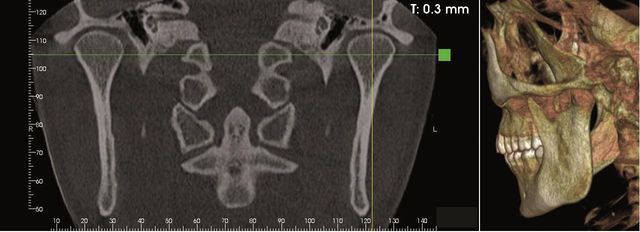

- Terapia antalgica

Si possono trattare le sindromi dolorose dell’ ATM e di altri disordini miofacciali con il manipolo Deep Tissue Handpiece™